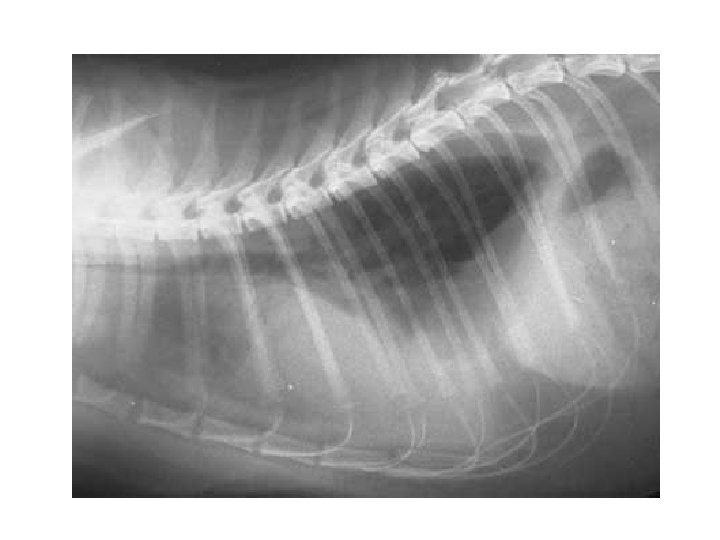

The lungs are the primary structures of the respiratory system. The lungs occupy almost the entire thoracic space. Each lung contains millions of aveoli and capillaries.

The lungs are encased in a serous membrane called the visceral pleura. The thoracic cavity is lined with another membrane called the parietal pleura. These membranes reduce the friction during repiration

The Diaphragm: This is a dome shaped musculomembranous partition separating the thoracic and abdominal cavity. It attaches to the lumbar and abdominal cavities. It attaches to the lumbar vertebra, lower ribs and sternum

The diaphragm is the primary muscle of respiration. During inspiration, it contracts, flattens and lowers. This increases the capacity of the thoracic cavity. On expiration the diaphragm relaxes and returns to it’s normal position